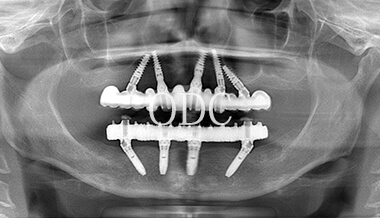

パノラマX線写真

術 後

術前・術後のパノラマX線写真です。上顎(オールオン4)は4本のインプラントにチタンフレームの上部構造が固定されているのがおわかりになると思います。下顎のインプラント埋入部位、上顎のインプラントの本数、再度写真をご覧いただくと、とてもインプラントが埋入されているとわからない程の外観、下顎の残存歯(元々の自分の歯)とも区別がつかない審美性が実現されています。